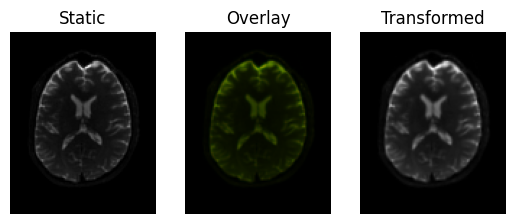

regtools.overlay_slices(

static,

transformed,

slice_index=None,

slice_type=2,

ltitle="Static",

rtitle="Transformed",

fname="transformed.png",

)

<Figure size 640x480 with 3 Axes>

Registration result.